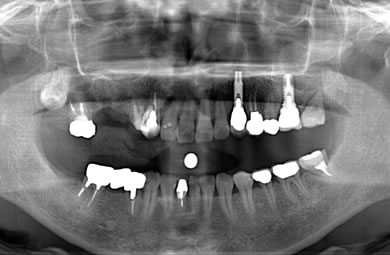

インプラントの症例写真 IMPLANT

スピードインプラント治療+セラミック治療

| 治療内容 | インプラント3本(抜歯即日スピードインプラント)、ハイブリッドセラミック5本 | ||||||||||||||||||||||||||||||||

| 総治療費 | 1,399,819円 | ||||||||||||||||||||||||||||||||

| 治療期間 | 8ヶ月 |